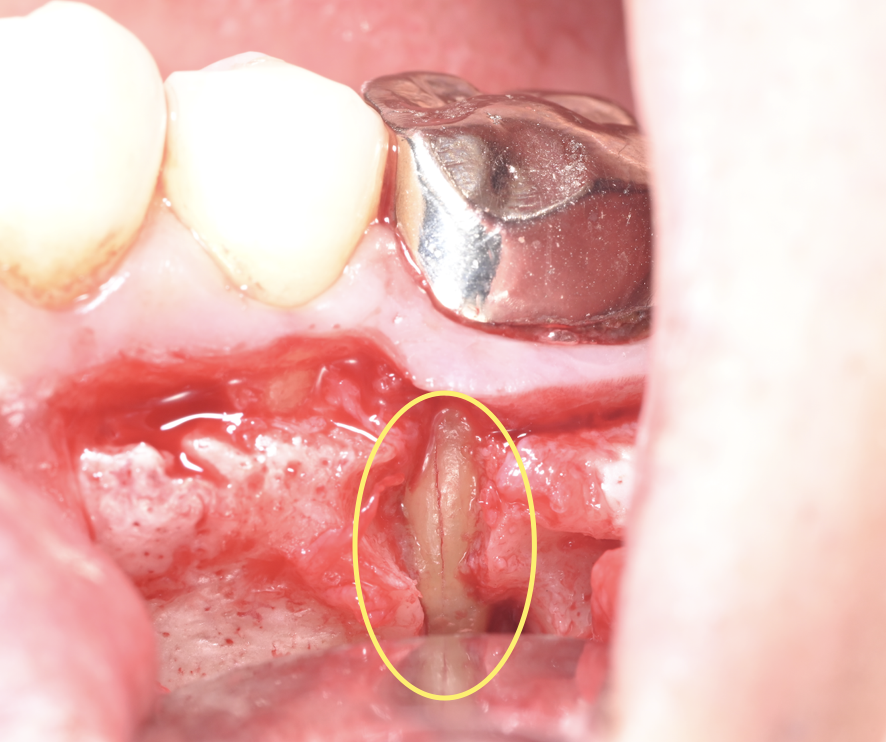

写真は神経内部をマイクロスコープで観察した写真になります。

歯の根の中に病巣があったので中を確認してみると、古い根管充填材(歯の神経内部に詰める詰め物)が中でドロドロになっていることがわかります。

この古い充填材料をマイクロスコープで確認しながら完全に取り除いていき、神経内部をきれいにしていきます。

このドロドロになった充填材料は神経内部にこびりついていることが多く、肉眼で完全に除去出来ていると思っても際にマイクロスコープで確認すると古い材料が多量に残存していることがかなりの確率であります。